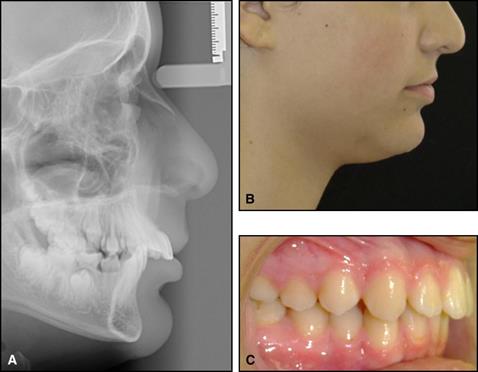

Fig. 4. A, cefalograma previo al tratamiento, B, fotografía de perfil posterior al tratamiento, y C, oclusión posterior al tratamiento de un paciente con una maloclusión de Clase II División 1 caracterizada por una sobrejet severa (10 mm) y una sobremordida profunda. Después de una fase inicial de tratamiento con un aparato funcional, la paciente y sus padres se negaron a continuar el tratamiento con aparatos fijos completos hacia la oclusión ideal de Clase I y la alineación dental. Aunque la oclusión está comprometida, la función y la estética (cara, perfil y sonrisa) fueron óptimas. Debido al delgado labio superior en relación con el labio inferior, una mayor reducción de la sobrejet (a través de la distalización del arco maxilar o el movimiento mesial del arco mandibular) probablemente resultaría en un paso inverso menos atractivo entre los labios.

La medicina personalizada obliga al diagnóstico adecuado, que debe abarcar la constitución del paciente, por lo tanto, "la armonía estructural y funcional y el bienestar de la persona total" (Ghafari, 1993). Conceptual y prácticamente, este enfoque puede producir un resultado del tratamiento que se desvía de la oclusión de clase I normal, en que se ha basado la salud ortodóntica u oclusal (Fig. 5). En algunos pacientes que rechazan el tratamiento quirúrgico ideal, la compensación limitada (para el camuflaje adecuado) apunta a una apariencia facial favorable en lugar de la oclusión de clase ideal. Por consiguiente, en lugar de alanar el perfil, se mantiene una sobrejet (Ghafari, 1997: Ghafari y Macari, 2014).